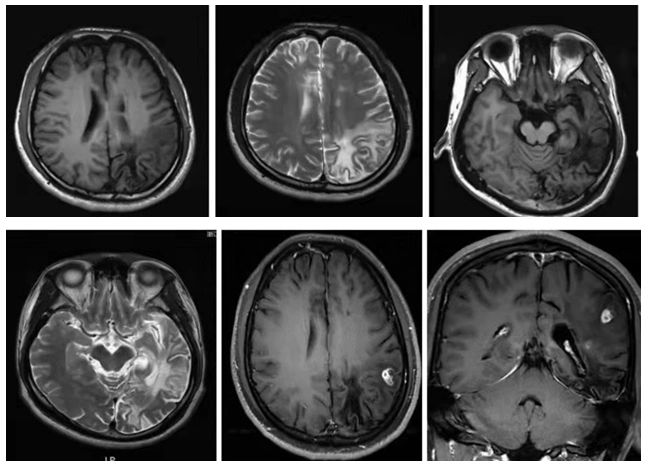

于人脑内所形成的中枢神经系统寄生虫病,其典 型的头颅磁共振影像为不